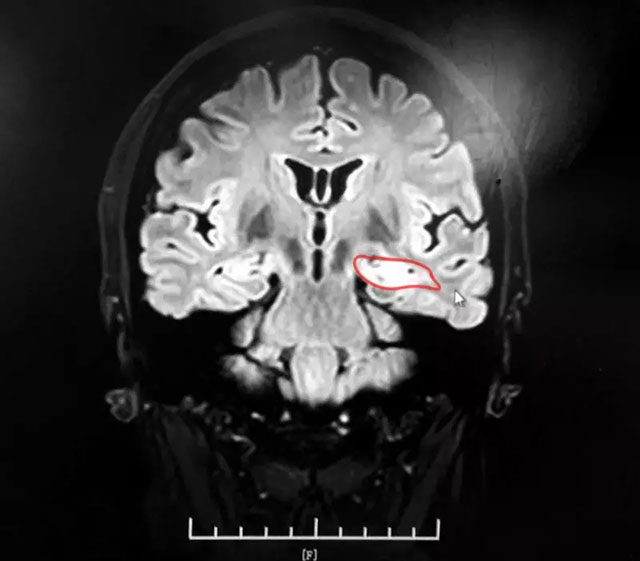

▲ 患者左側海馬病灶區(qū)

為了確定患者是否患有癲癇病,在入院的第一天蘇女士就做了腦電圖檢查,但檢查結果卻差強人意,和患者第一次腦電圖檢查結果一樣,并未發(fā)現(xiàn)患者任何異常情況;隨后患者又進行了頭顱MR檢查,檢查提示患者左側海馬異常。為了進一步明確病因,戴主任建議患者進行MR海馬增強掃描:MRI平掃+MRS+MRSI,影像提示:1、患者左側海馬信號增高;2、MRS 雙側海馬Cho峰稍升高(左側NAA/Cr+Cho=0.42;右側NAA/Cr+Cho=0.52),結合臨床,以及檢查結果,戴主任認為患者患癲癇病的幾率非常大。

為了更好的確定治療方案,戴秀珍主任邀請功能神經(jīng)外科專家楊忠旭博士進行會診,楊忠旭博士是藍十字功能神經(jīng)外科特需專家,他是癲癇外科創(chuàng)始人之一。經(jīng)過專家會診、討論,并結合患者影像檢查結果及立體腦電監(jiān)測結果,都明確顯示患者左側海馬信號增強,加之患者兩次典型癲癇大發(fā)作癥狀,最終確定患者為復雜性癲癇,一致認為應先對其進行癲癇藥物治療,觀察其治療效果,如果藥物控制不佳可考慮手術治療癲癇。